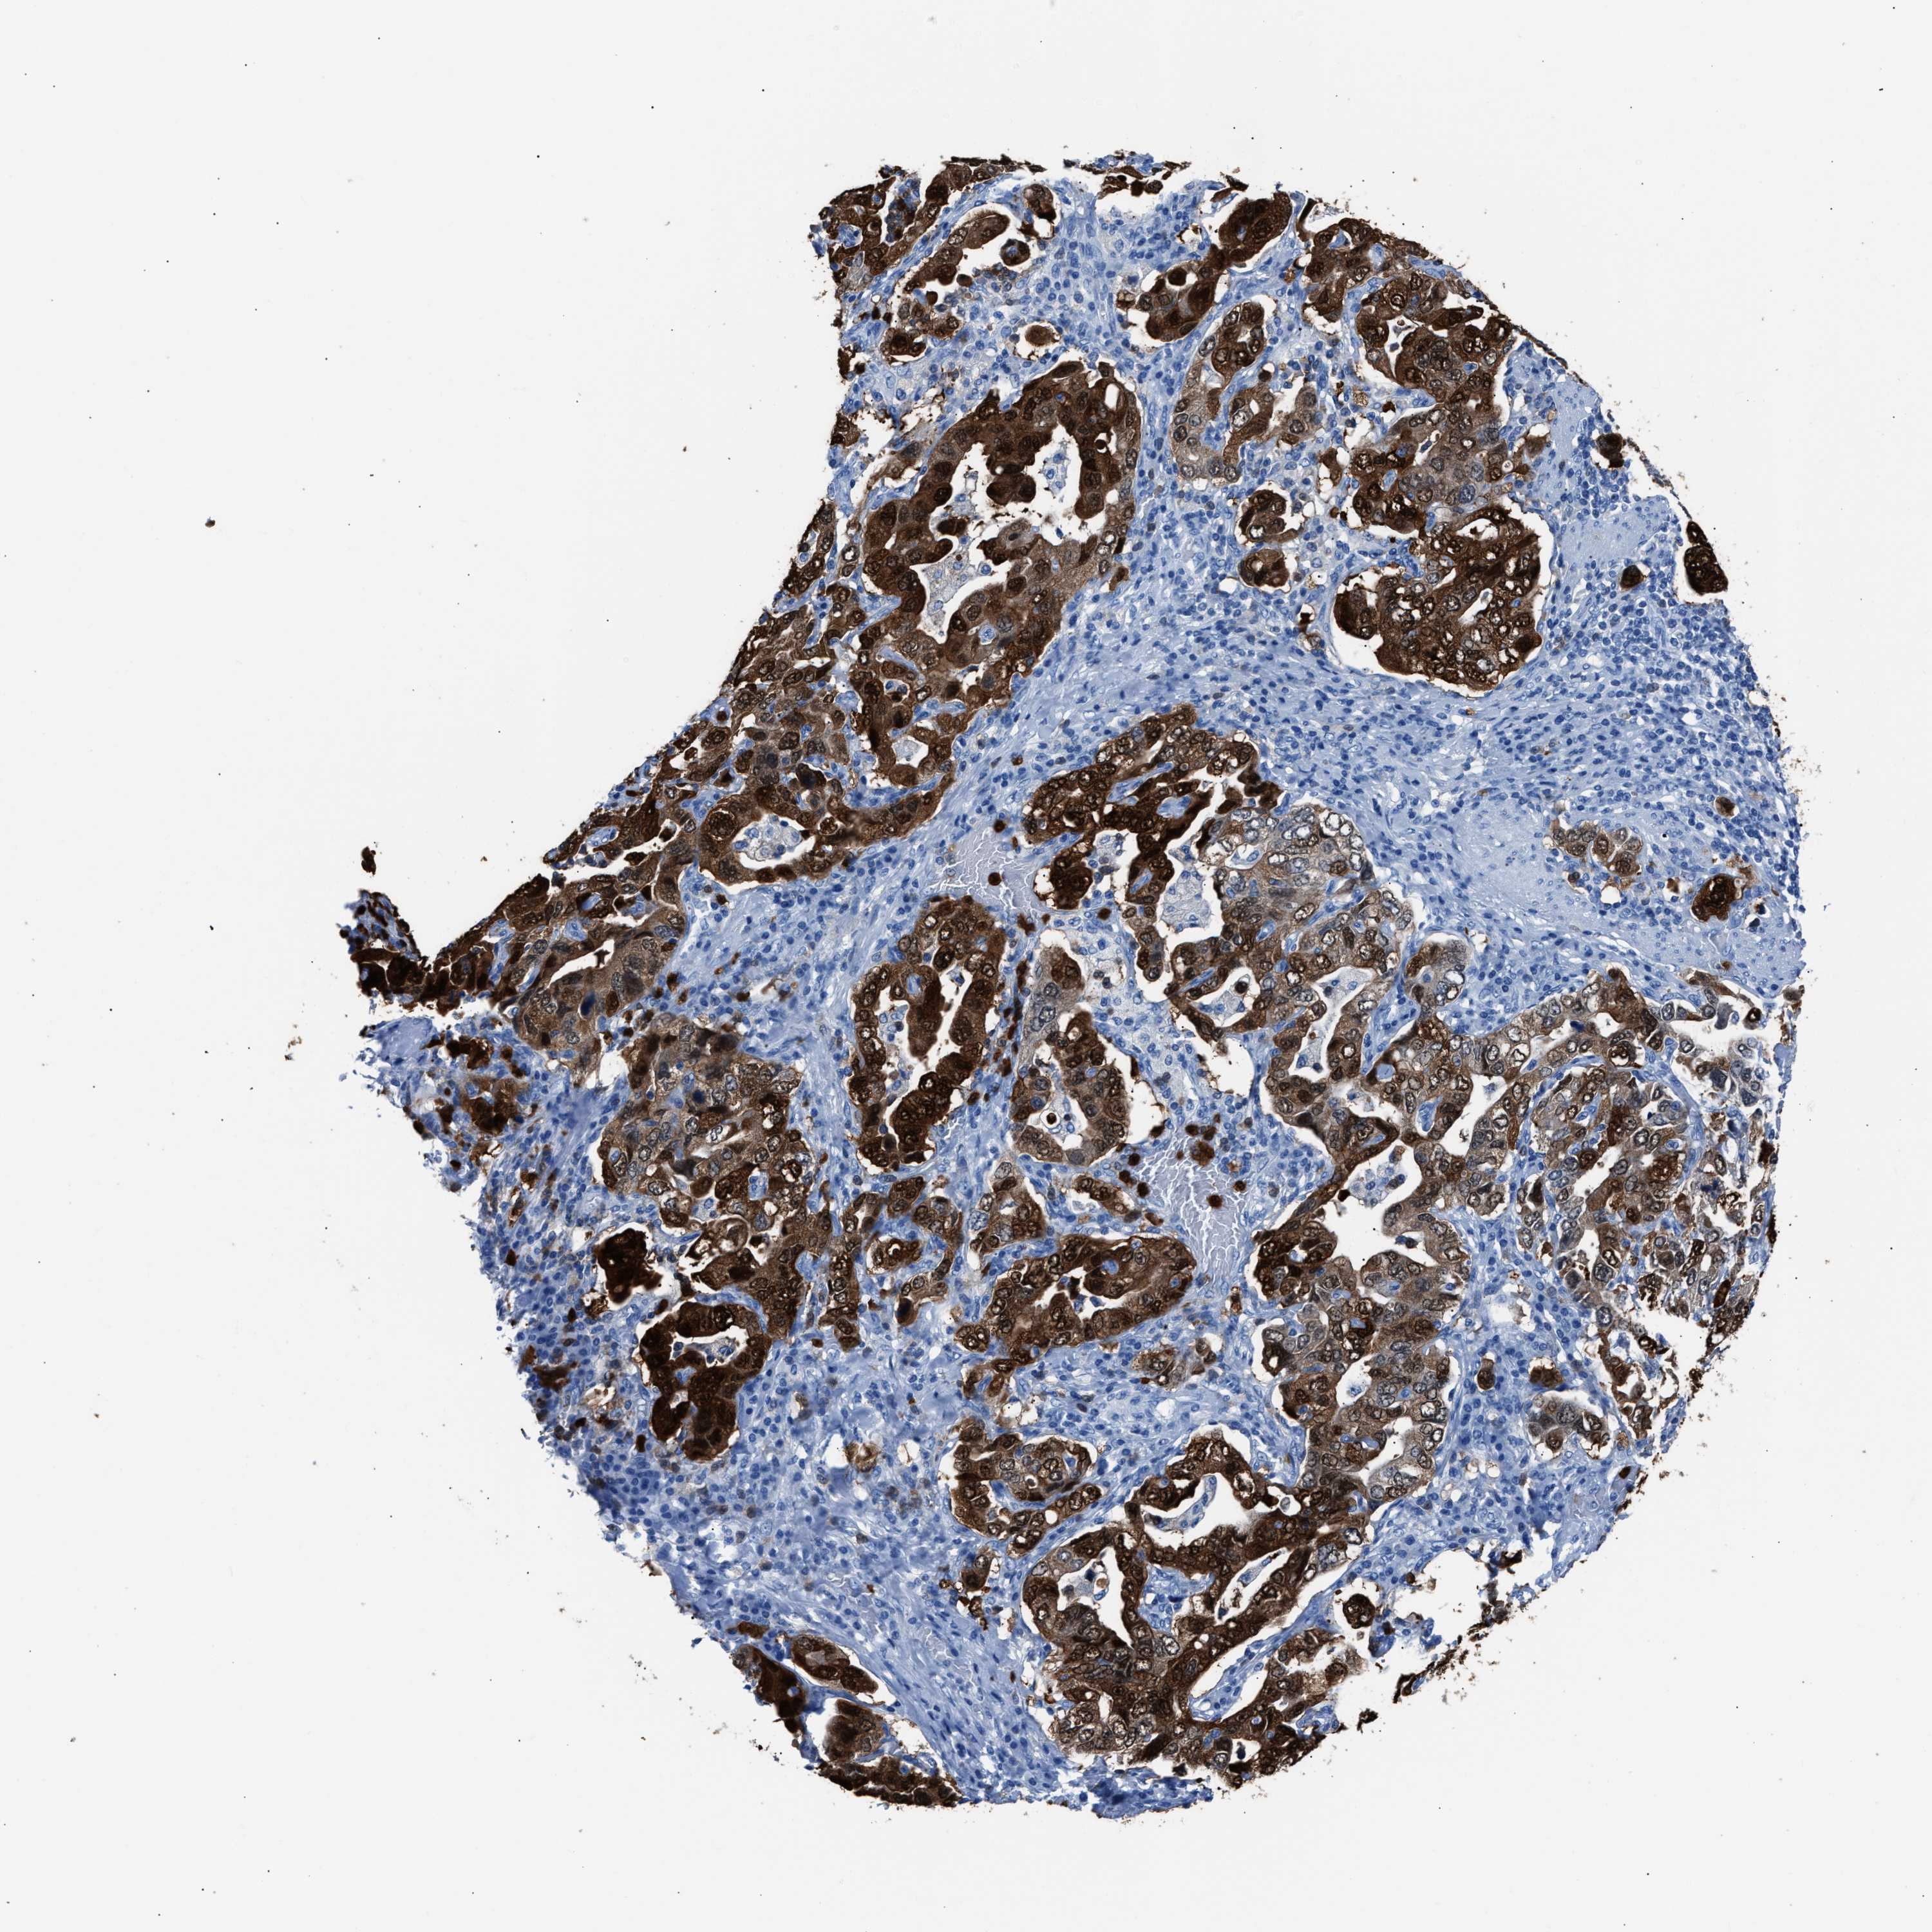

STOMACH CANCER - Protein expressioni

A mouse-over function shows sample information and annotation data. Click on an image to view it in a full screen mode. Samples can be filtered based on level of antibody staining by selecting one or several of the following categories: high, medium, low and not detected. The assay and annotation is described here.

Note that samples used for immunohistochemistry by the Human Protein Atlas do not correspond to samples in the TCGA dataset.

Antibody stainingi

Antibody staining in the annotated cell types in the current human tissue is reported as not detected, low, medium, or high, based on conventional immunohistochemistry profiling in selected tissues. This score is based on the combination of the staining intensity and fraction of stained cells.

Each image is clickable and will lead to virtual microscopy that enables deeper exploration of all samples and also displays staining intensity scores, fraction scores and subcellular localization as well as patient and tissue information for each sample.

Antibody HPA019502

Staining

High

Medium

Low

Not detected

Intensity

Strong

Moderate

Weak

Negative

Quantity

>75%

75%-25%

<25%

None

Location

Nuclear

Cytoplasmic/membranous

Cytoplasmic/membranous,nuclear

Adenocarcinoma, NOS